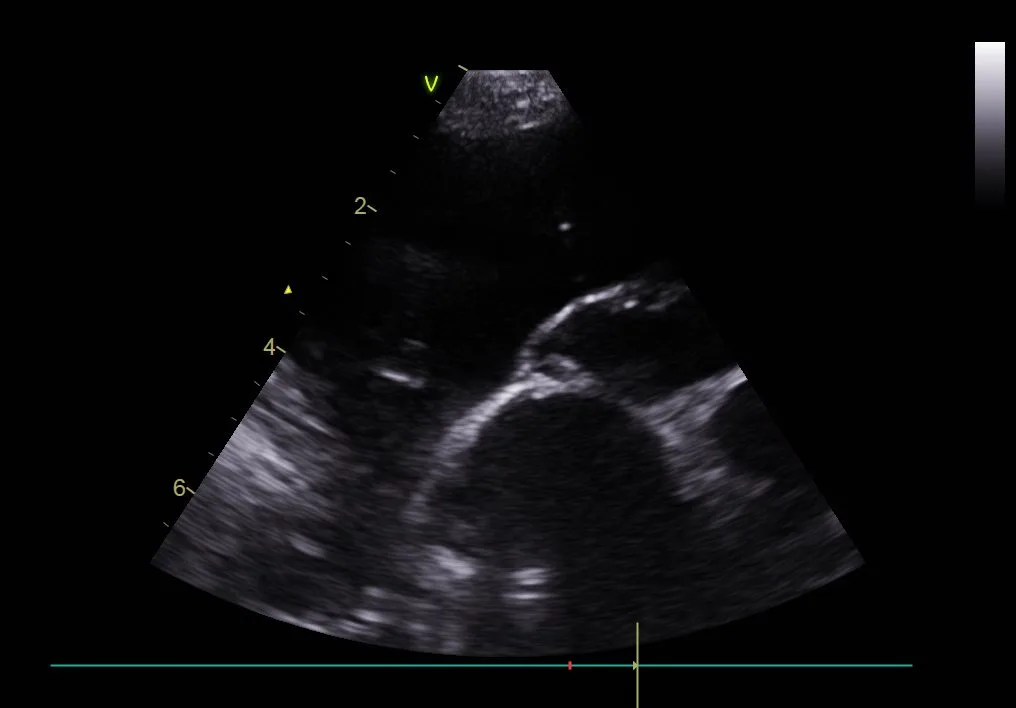

Pleural effusion can be easily identified on radiographs (Figures 1 and 2) and ultrasound (Figure 3). In patients with respiratory distress, oxygen and sedation should be administered before standard aseptic, often ultrasound-guided, thoracocentesis is performed. Removal and collection of fluid can quickly improve oxygenation and ventilation and allow clinical investigation to determine the cause of effusion.

Thoracic ultrasound of the left side of the chest in a dog with marked pleural effusion